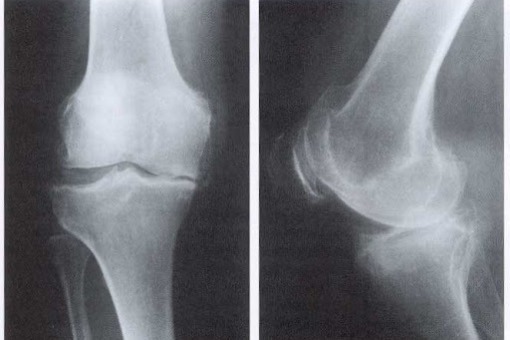

Blokada interleukiny-1-beta może spowolnić postęp choroby zwyrodnieniowej stawów

Interleukina-1-beta jest kluczowym graczem w procesie zapalnym choroby zwyrodnieniowej stawów, a jej hamowanie może spowolnić proces chorobowy, zgodnie z analizą danych z badania CANTOS.